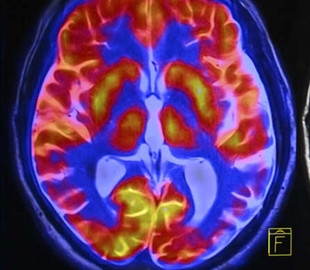

Исследователи из Кардиффского университета позаимствовали идеи из популярных приложений для знакомств, в частности Tinder, чтобы обучить добровольцев определять некачественные снимки мозга. С новым приложением тысячи сканированных изображений исследования можно анализировать намного быстрее, что поможет в ряде исследований.

Здесь на помощь приходит новое приложение, разработанное Кардиффским университетом и Национальной академией программного обеспечения. Используя реальные изображения мозга пациентов с болезнью Альцгеймера, приложение обучает добровольцев распознавать правильную форму свода на отсканированном изображении.